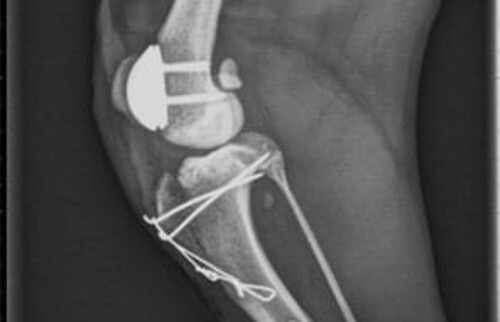

Abbildung 2: Die Korrektur der Kniescheibenlockerheit

PGR von KYON

Abbildung 3: PGR von KYON